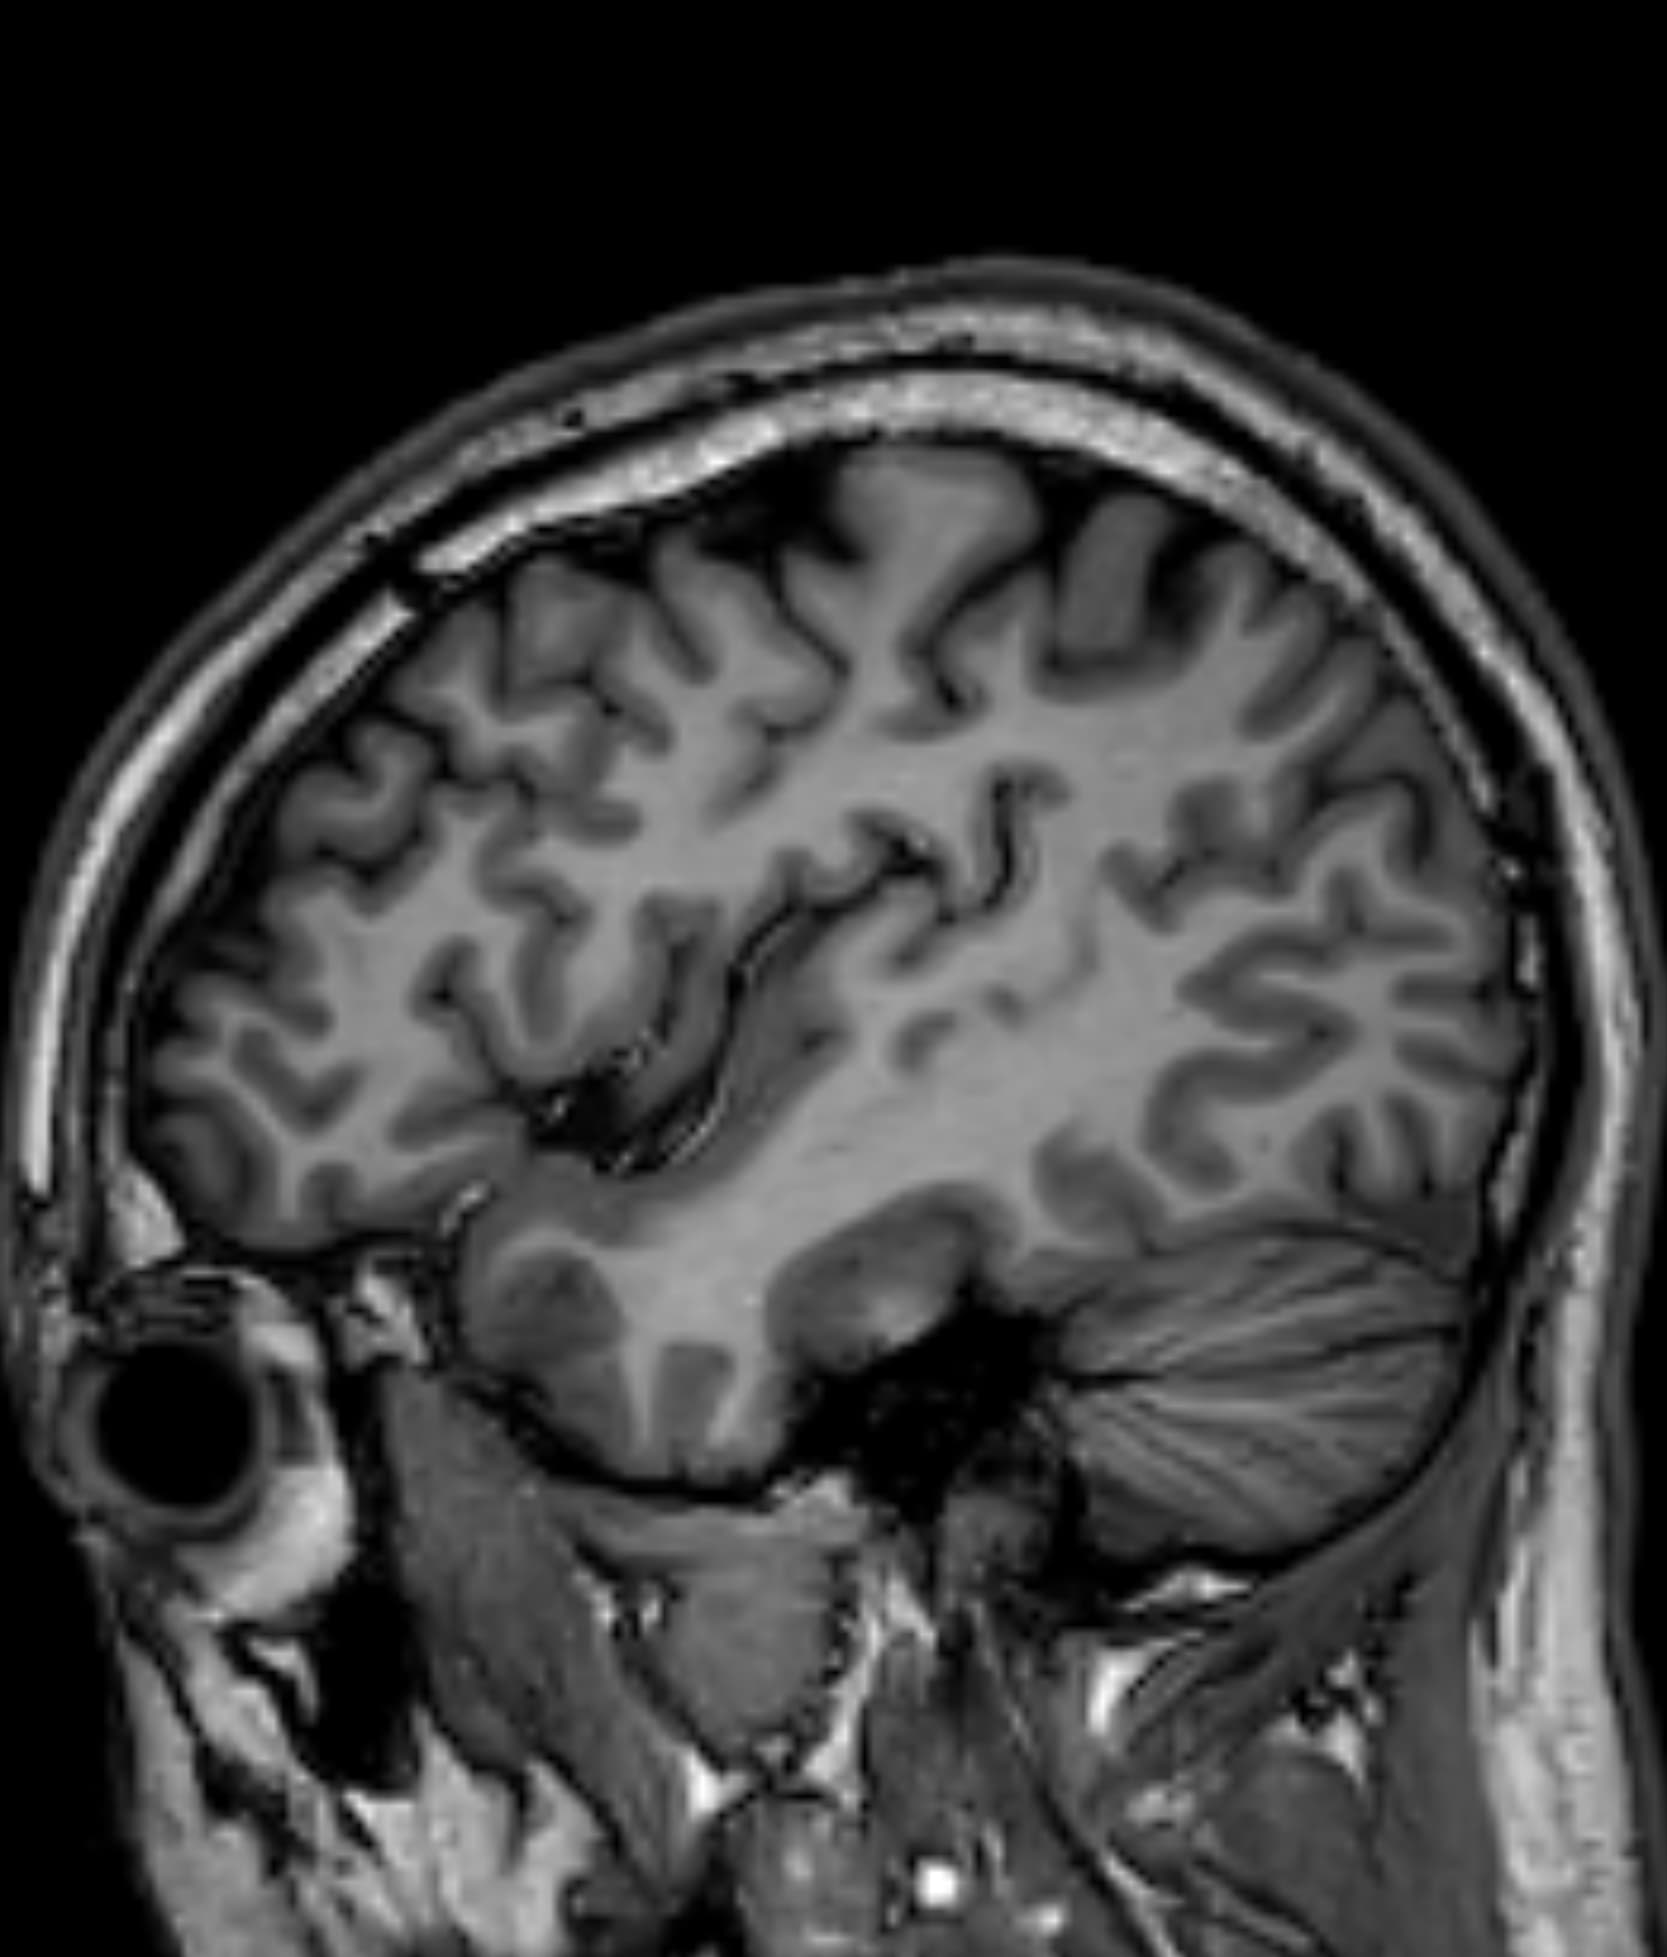

Δείτε πραγματικά παραδείγματα του SwiftMR™ σε διάφορα συστήματα MRI και ανατομικές περιοχές

Scan time 03:14

Scan time 02:07

Scan time 03:08

Scan time 1:12

Scan time 04:53

Scan time 1:46